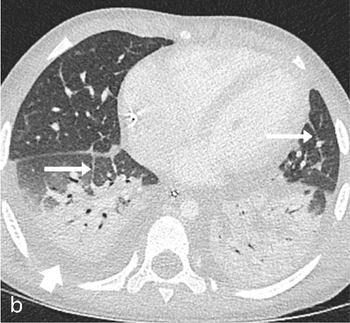

Research reveals lung findings not typically associated with viral pneumonia.

Side-by-side images show lung ultrasound pinpoints same findings as low-dose chest CT.

After 2.5 hours, providers could successfully identify lungs with pathological patterns indicative of viral infection.